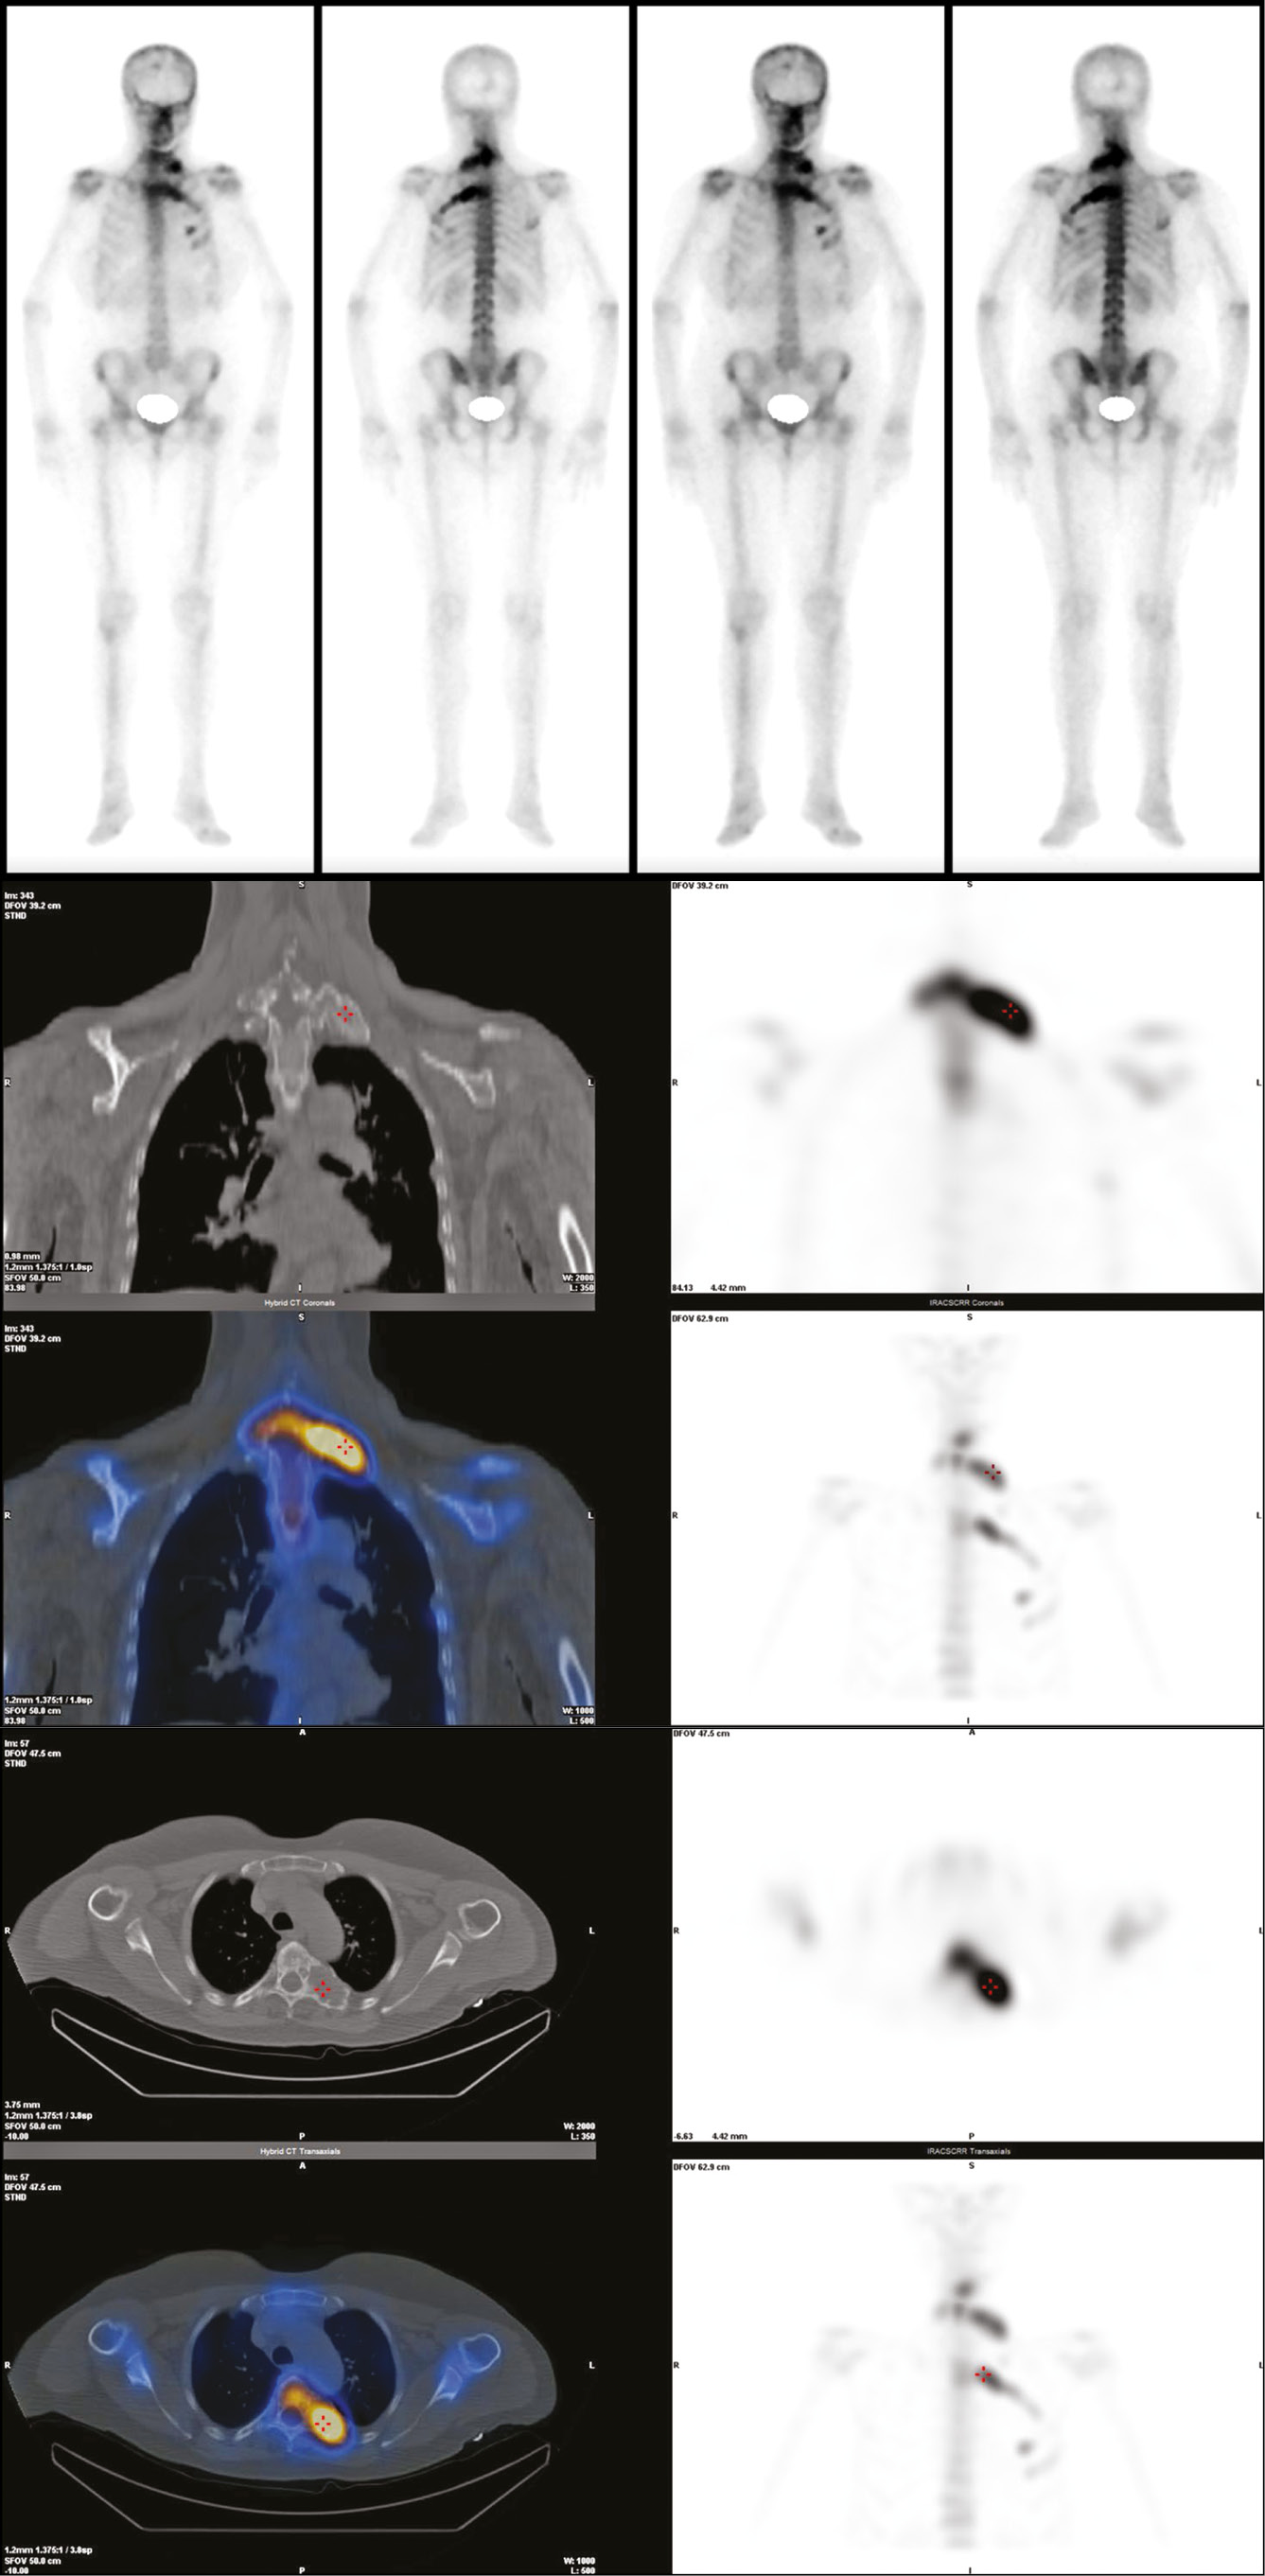

Additionally, the presence of a marked metabolic activity at these levels was confirmed by the SPECT-CT scan, which showed two areas of intense and pathological focal accumulation of the osteotropic tracer (99mTc-HDP) in the left paravertebral side. The upper one, corresponds to the first dorsal vertebra, with an SUV max of 39.91, and the other at D5-fifth left rib with an SUV max of 47.06 (Fig. 5).

Fig. 5. The whole body SPECT-CT confirmed the involvement of the above-mentioned bone segments and no other particularly shows two areas of high pathological focal accumulation of the osteotropic tracer (99mTc-HDP) in the left paravertebral side (D1 and D5-fifth left rib).